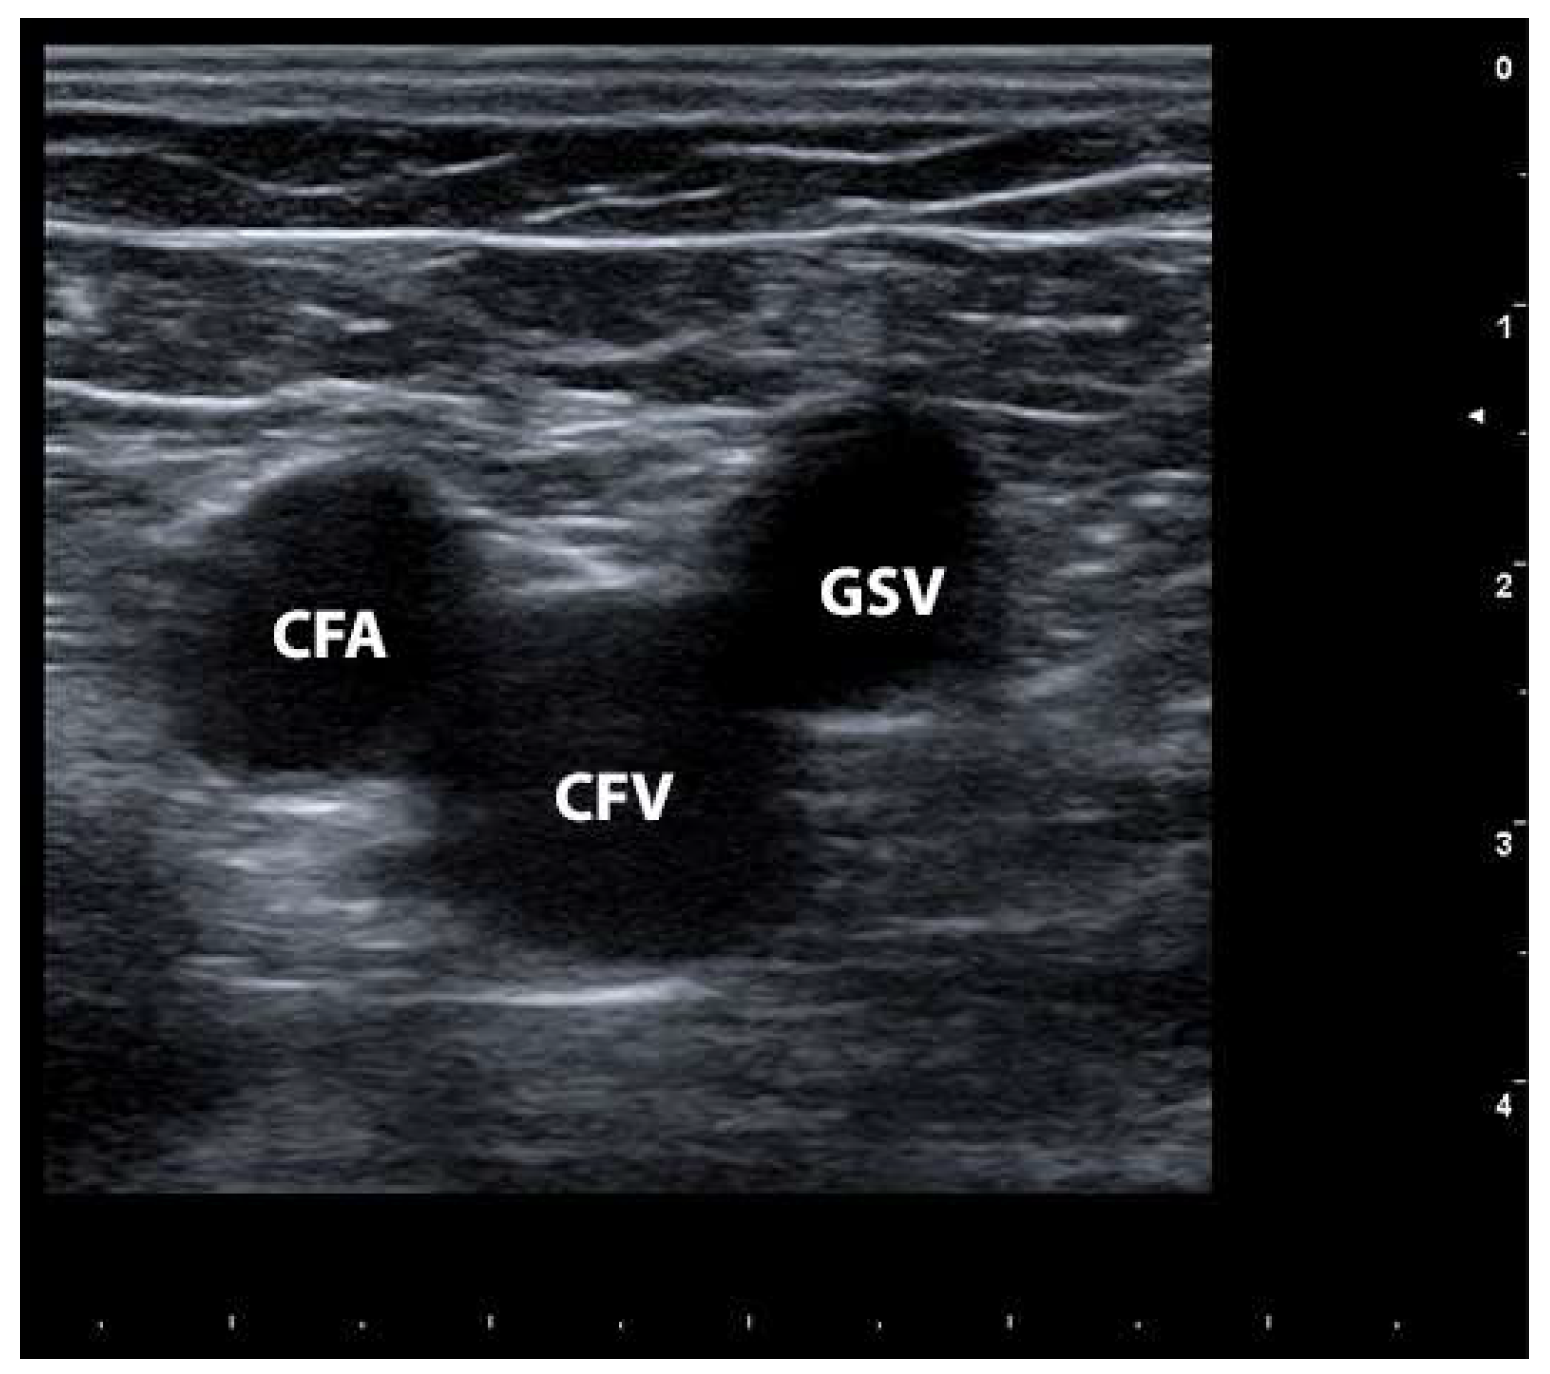

1.1. Doctor, How Are the Veins of the Lower Limbs Made and Which Ones Get Sick?

1.4. How Is It Possible to Diagnose CVD?